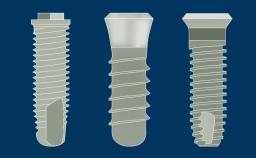

Practising Implant Dentistry and Self Directed Learning

Clinical photography is a powerful tool in implant dentistry. In these three photos, photography is being used to document the before, during and after stages in removal of a failed implant prosthesis. Clinical photography is also invaluable in communication between all parties to dental treatment including patients, laboratory technicians, and colleagues.

Modern digital photography is user-friendly for dentists and allows rapid transfer of information. This Module will outline and explain a suitable camera setup for digital clinical photography on a daily basis and demonstrate its clinical use.